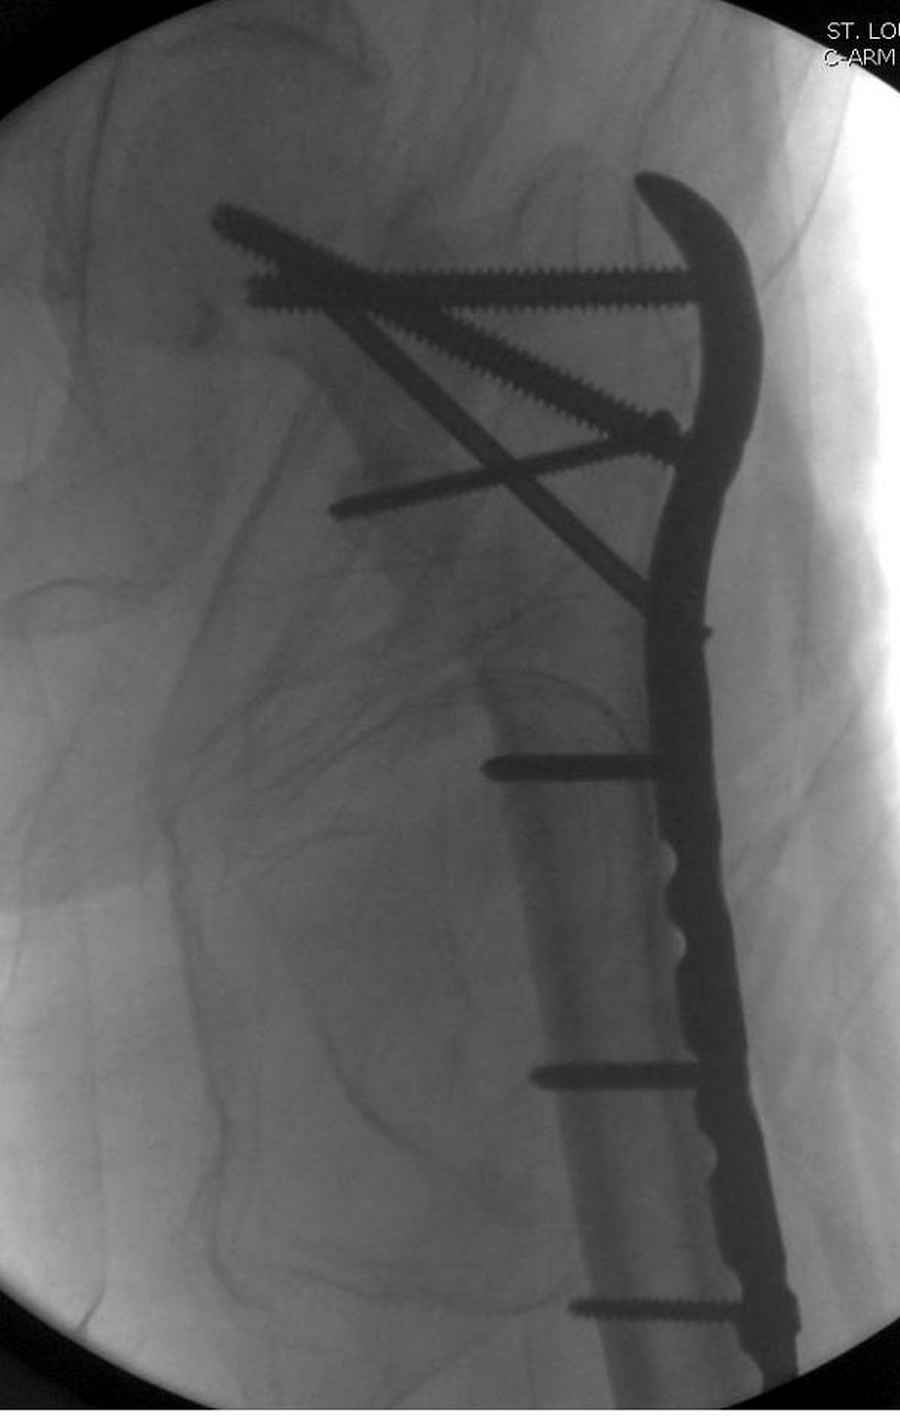

Здесь пара случаев фиксации похожих переломов:

первый высокоэнергетическая травма 36 лет